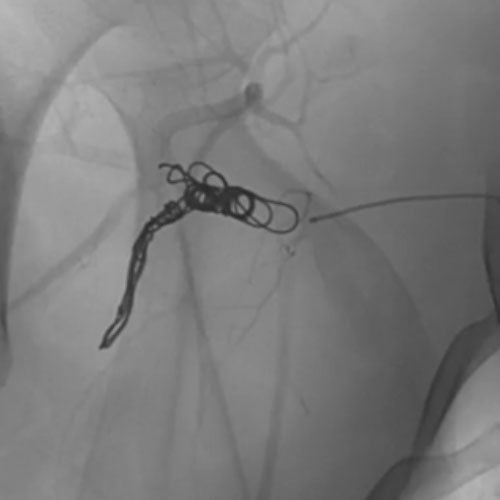

Ruby Standard Coil shown in iliac right artery Ruby Standard Coil shown in right internal iliac artery

Right Internal Iliac Artery

5 Ruby Standard 6x20

Embold Fibered Coil shown in left internal iliac artery Embold Fibered Coil shown in left internal iliac artery

Left Internal Iliac Artery

3 Embold Fibered Coil 6x20

3 vs 2 Coils